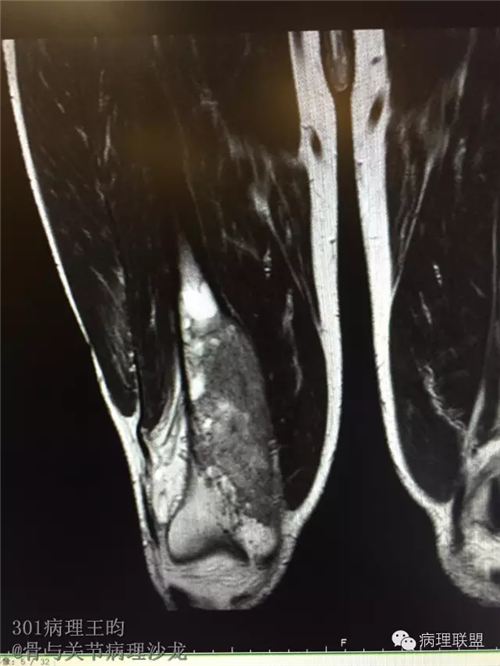

右股骨髓内高分化低级别骨肉瘤or骨纤维异常增殖症(Fibrous Dysplasia)?

男,36岁,活动后疼痛,发现右股骨远端肿瘤。